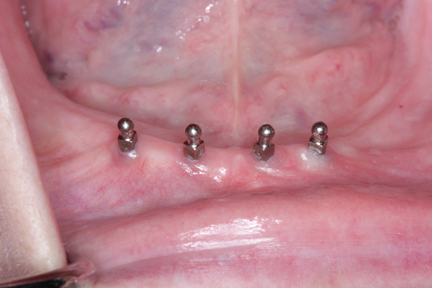

![]() Mini-implant được sử dụng để nâng đỡ hàm giả tháo lắp. |

Cấy ghép mini-implant thường được lựa chọn trong những trường hợp vị trí cấy ghép không chịu lực nhai lớn, thông thường hay chỉ định mini-implant cho các răng trước và trong trường hợp làm các tựa nâng đỡ cho các hàm giả tháo lắp phủ trên implant. Quyết định lựa chọn hình thức cấy ghép nào, implant truyền thống hay mini-implant để thay thế cho răng đã mất cần phải được cân nhắc, lựa chọn hết sức cẩn thận. Do đó, bác sĩ nha khoa nên tư vấn cho bệnh nhân của mình những ưu thế cũng như nhược điểm của cả hai hình thức cấy ghép để giúp bệnh nhân có thể lựa chọn hình thức cấy ghép tốt nhất. Một điều quan trọng không kém là sau khi tiến hành cấy ghép, bệnh nhân cần phải được kiểm tra định kỳ để đảm bảo không có các vấn đề phát sinh như viêm lợi hay tổ chức xung quanh vùng cấy ghép, đồng thời cũng để kiểm tra sức khỏe răng miệng tổng thể của bệnh nhân.